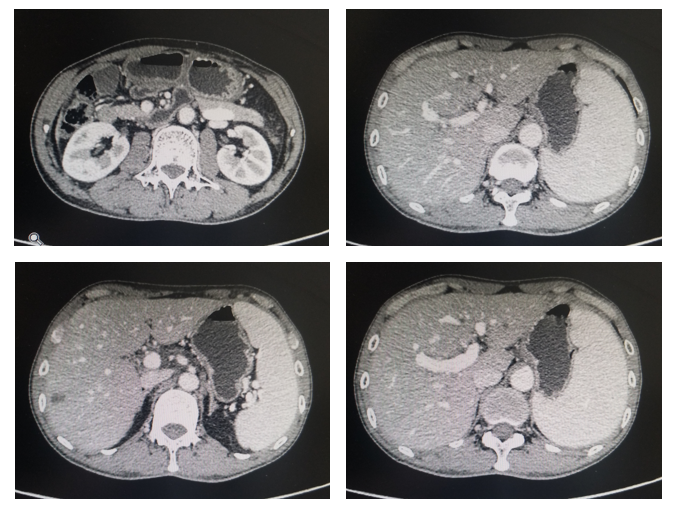

上腹CT:肝内多发低密度结节,胃窦区胃壁增厚(图1)。

图2. 腹部CT平扫+强化(2019年10月)

影像科:从CT看,该患者胃窦区胃壁增厚,肝内多发结节,结合胃镜及病理结果,考虑原发性胃癌诊断明确,肝脏病灶为转移性病灶,因此,考虑胃癌晚期伴多发肝转移诊断成立。

评估:治疗后3月和5月复查腹部CT情况(图2和图3).

图3. 腹部CT平扫+强化(治疗后2月,2020年1月)

图4. 腹部CT平扫+强化(治疗后5月,2020年3月)

影像科:根据患者治疗前、治疗后首次及再次复查CT看,原发病灶胃壁增厚明显减轻,肝转移病灶明显缩小,部分病灶消失,首次CT判效PR,再次复查CT确认PR。提示内科治疗有效。